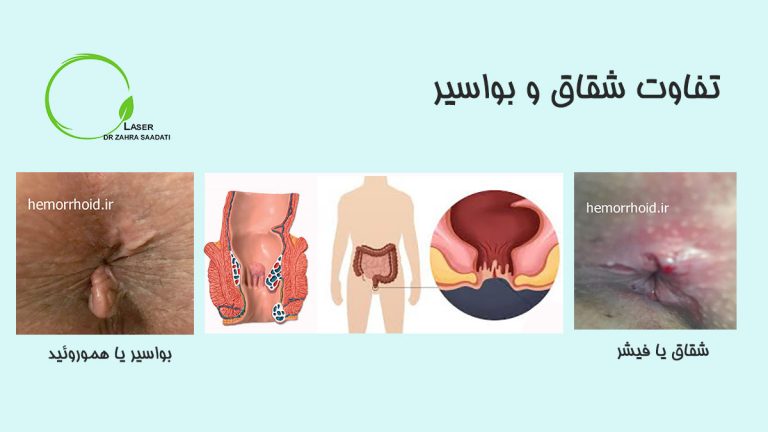

تفاوت شقاق و هموروئید برای تشخیص و درمان ناراحتی های مربوط به ناحیه ی آنال (مقعد ) بسیار حائز اهمیت…